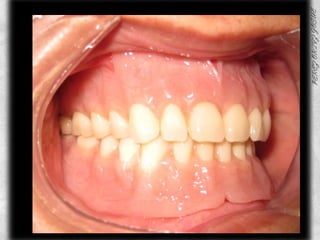

ANTECESDENTES PROSTODONTICOSPROSTODONCIA SUPERIOR CON 7 AÑOS DE USO Y DESGASTES EN TODOS LOS DIENTES, SIN PRESENCIA DE SARRO Y CON MOVILIDAD

PROSTODONCIA DEL PACIENTE INFERIORPROSTODONCIA INFERIOR CON BUENA ANATOMIA OCLUSAL EN LOS MOLARESCON 6 MESES DE USOBUEN SELLADO, SOLO SE HIZO LA INFERIOR

ANTERIOR DE PROSTODONCIADOS COLORES DIFERENTES DE ACRILICOSANTIESTETICA

PROTESIS TERMINADA

AJUSTE OCLUSAL

COMPARATIVOS